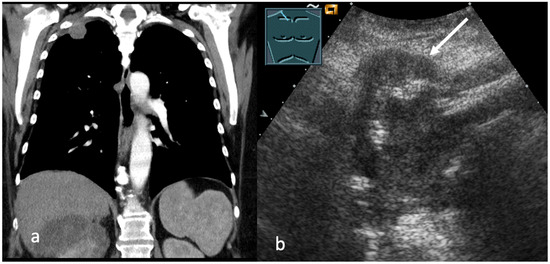

Emerging Role of Transcutaneous Ultrasound in the Diagnostic of Lung Cancer

by Corinna Trenker-Burchert, Marius Dohse, Hajo Findeisen, Andreas Schuler and Christian Görg

Cancers 2025, 17(23), 3873; https://doi.org/10.3390/cancers17233873 - 2 Dec 2025

Lung cancer is one of the most commonly diagnosed malignancies worldwide and continues to be a leading cause of cancer-related mortality. Precise staging is crucial for predicting outcomes and directing treatment decisions. Current international guidelines mainly recommend imaging techniques like CT and PET-CT, [...] Read more.

Lung cancer is one of the most commonly diagnosed malignancies worldwide and continues to be a leading cause of cancer-related mortality. Precise staging is crucial for predicting outcomes and directing treatment decisions. Current international guidelines mainly recommend imaging techniques like CT and PET-CT, with limited references to transcutaneous ultrasound, which is only suggested in particular clinical cases. Ultrasound provides real-time imaging, high resolution in near-field structures, and the ability to assess thoracic wall infiltration, supraclavicular and cervical lymph nodes, pleural effusions, and metastatic lesions. Furthermore, ultrasound-guided biopsies can enable quick and safe histological confirmation of accessible lesions. Based on these advantages and a review of current literature, we propose that integrating ultrasound into staging algorithms could improve diagnostic efficiency, decrease invasive procedures, and support prompt treatment planning. We also highlight the need for further research in this area. Full article

Show Figures

Figure 1